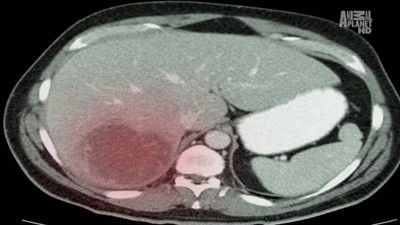

A schoolteacher deals with an amoeba that eats at his liver and causes him high fever, abdominal pain, sweating, and chills. A young dancer gets worms from eating contaminated pork in her muscle tissue, causing her to get hives all over her body and her limbs to become stiff and painful. A retiree gets scabies from mites he got from staying in the hospital in the past.